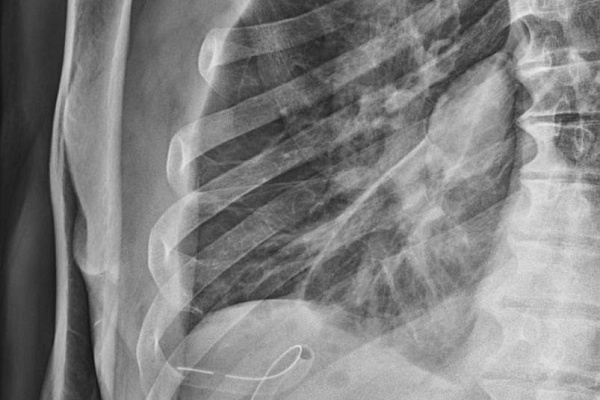

Правда, ситуации разные. Если с экрана нам рассказывают о последствиях травмы грудной клетки, то врачи травмбольницы имеют дело с грозным заболеванием, при котором плевральная полость заполняется гнойным содержимым. Из-за этого лёгкое сдавливается и не может полноценно участвовать в дыхательном процессе. Больные испытывают постоянную дыхательную недостаточность, у них развивается системная воспалительная реакция, интоксикационный синдром, в худшем случае – сепсис и полиорганная недостаточность.

Эмпиема плевры – вторичная патология, возникает как осложнение, в том числе, после вирусных и бактериальных пневмоний. За последние два года торакальные хирурги Сургутской травмбольницы внедрили и поставили на поток высокотехнологичную малоинвазивную методику оперативного лечения этого заболевания. Она пришла на смену тяжелым обширным вмешательствам на грудной клетке с длительным и сложным послеоперационным ведением больных.

Торакоскопическая методика кропотливая и технически непростая. Через три разреза от 0,5 до 1 сантиметра хирурги специальным инструментом разрушают и удаляют всю патологическую ткань – гнойные полости, спайки, шварты, фибринозные наложения. Двигаться необходимо очень осторожно, чтобы не повредить лёгкое. Работа проводится при повышенной из-за воспаления кровоточивости, а на отдельных участках кратно усложняется множеством тонких и уязвимых сосудов.